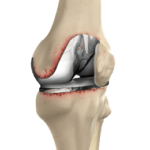

بخشی از نمونه کارها

نمونه کارهای قبل و بعد